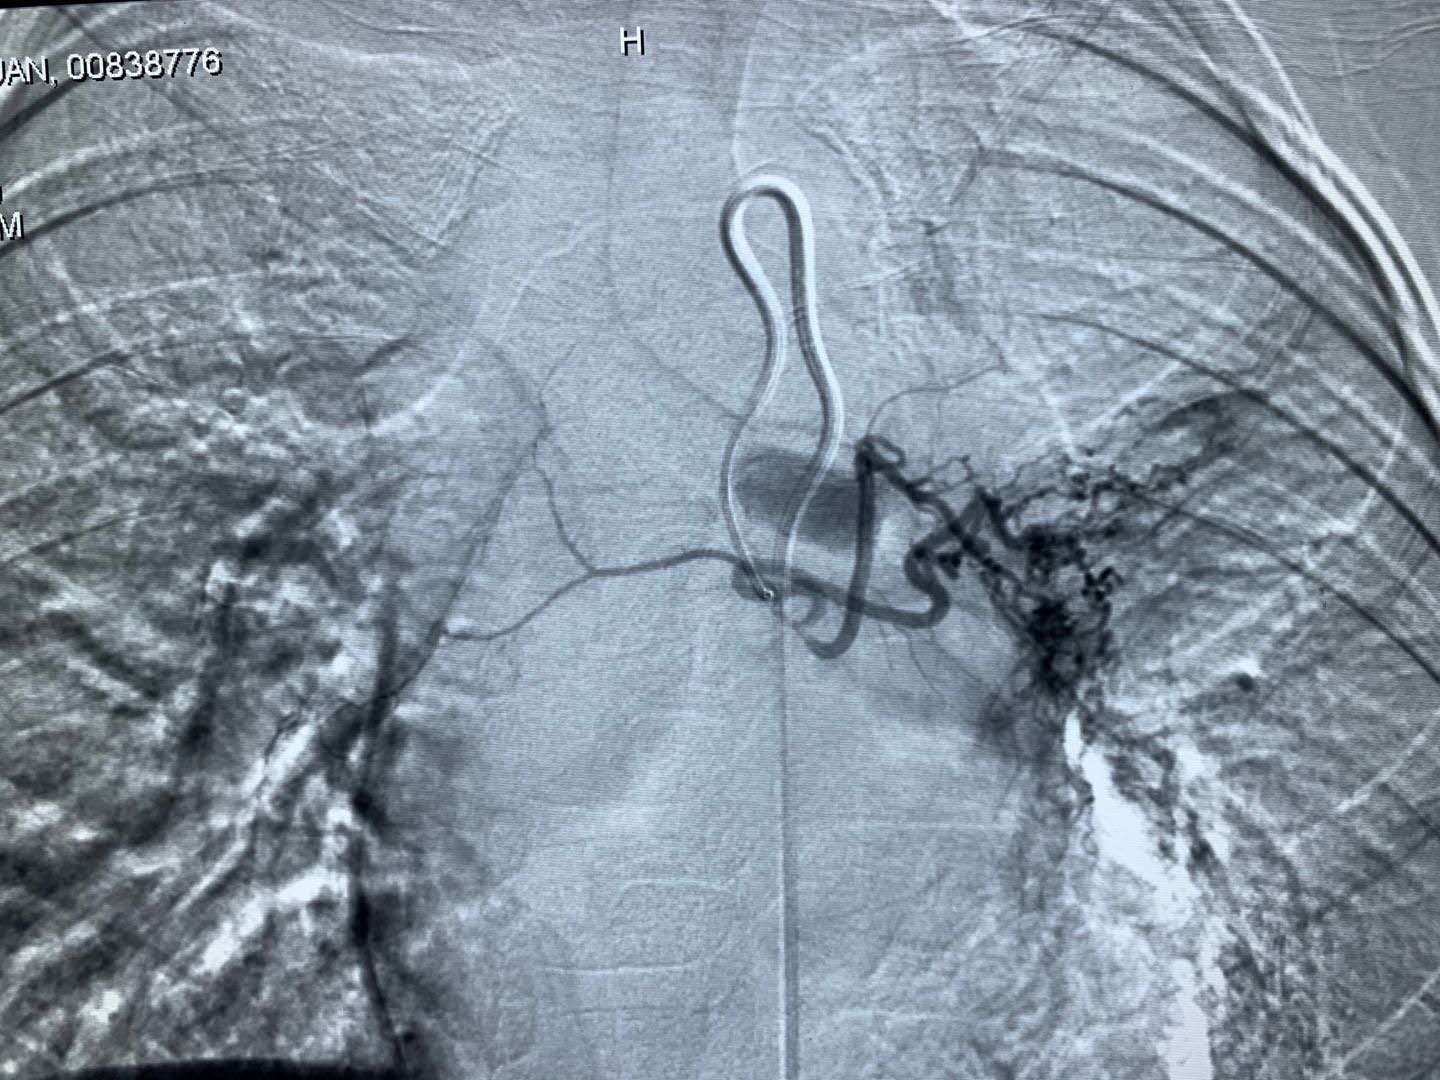

支气管动脉栓塞

科室立即请介入血管外科、心胸外科及成人呼吸科会诊,并经家属同意后,为小涵制定了肿物处血管栓塞再经支气管镜切除并活检的诊疗方案,但是孩子年龄小,找到供应肿物的血管不容易,栓塞成功更是困难。介入血管外科经过努力,成功为小涵施行了支气管动脉造影+栓塞术,开启了孩子康复的希望之门,术后,儿童呼吸介入团队在支气管镜下为小涵切除肿物,术中预先留置球囊预防急性出血,手术取得成功,孩子左下叶通气功能迅速恢复。术后病检结果显示,为透明细胞糖瘤,属于儿童罕见的良性肿瘤。又通过第4次支气管镜,将左肺上叶残留肿物清除,小涵左肺上叶得以成功保住,康复出院。